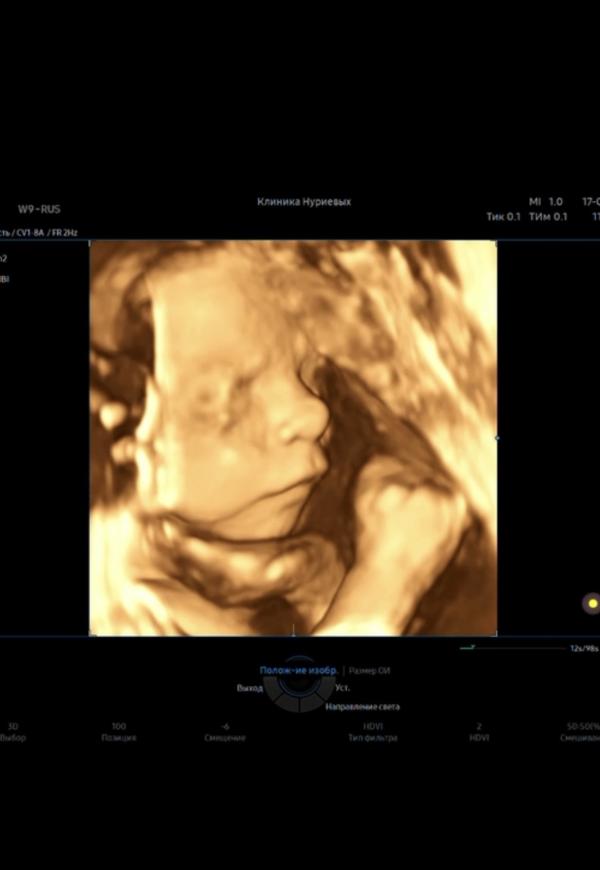

25 недель, ходили на узи) все в норме ☺️ Малышка похорошела с прошлого узи, щечки наела) Меня покорили губешки🥰 В прошлый раз меня так сильно не умилило это всё, как сейчас))

Это скрин с 4д) с видео) да вроде не большая) 753 г (если вы про ребенка)))

Какие они милые на этих снимках🥹

Очень интересно потом сравнить черты будет